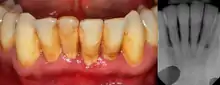

Dental plaque is a microbial biofilm which forms on teeth. This biofilm may calcify and harden, termed calculus (tartar). Plaque tends to build up around the gingival margin (the gumline) and in gingival crevices or periodontal pocket (below the gumline). The release of waste products from the bacteria living in the biofilm causes an inflammatory response in the gums which become red and swollen, bleeding easily when disturbed. This is termed plaque-induced gingivitis and represents the most common form of gingival disease.[2] This inflammatory response in the host can be strongly influenced by many factors such as hormonal fluctuations, drugs, systemic diseases, and malnutrition;[3] which may allow further subdivision of plaque-induced gingivitis (see table).

Periodontitis

The defining feature of periodontitis is connective tissue attachment loss which may manifest as deepening of periodontal pockets, gingival recession, or both. This loss of support for the teeth is essentially irreversible damage. Chronic periodontitis is generally slow to moderate in terms of disease progression, although short bursts of increased tissue destruction may occur. Ultimately, tooth loss may occur if the condition is not halted. It is termed localized when less than 30% of sites around teeth are involved, and generalised when more than 30% are involved. clinical attachment loss can be used to determine the severity of the condition, where 1-2mm is slight, 3-4mm is moderate and more than 5mm is severe.[2]